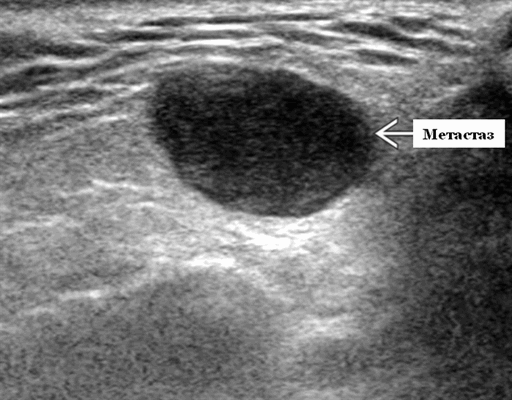

- Одиночные или множественные гипоэхогенные образования при известном распределении внутрипаротидных лимфоузлов.

- На УЗИ определяется аномальная внутренняя архитектура ± эхогенные ворота, эхогенность однородная или неоднородная с внутренними кистозными участками в некротических узлах

Визуализация. Общие особенности. Само по себе ультразвуковое сканирование метастазов в околоушные лимфоузлы неспецифична. Одиночные или множественные околоушные образования. Хорошо выраженный или плохо выраженный лимфоузел (экстранодальное распространение), однородный или неоднородный с внутренним некрозом. На УЗИ с ЦДК внутриузловая васкуляризация или усиление кровотока. Патология связана с известным первичным раком, часто в прилегающей коже или региональной области головы и шеи. Околоушные и перипаротидные узлы: узловая станция 1-го порядка при плоскоклеточной карциноме кожи (ПКК) и меланоме латеральной части волосистой части головы, ушной раковины / наружного слухового прохода и передней части лица

Размер. Обычно 1-3 см

Морфология. Форма яйцевидная или круглая. Край на УЗИ хорошо выраженный или (при экстранодальном распространении) инфильтративный

Результаты ультразвукового исследования слюнной железы

Серошкальное УЗИ. Одиночные или множественные гипоэхогенные образования в известном распределении внутрипаротидных лимфоузлов. Хорошо выраженный или слабо окаймленный (экстранодальное распространение). Экстранодальное распространение. Обратите внимание на местную инвазию интрапаротидной наружной сонной артерии (ВСА), ретромандибулярной вены или экстрапаротидных мягких тканей. Аномальная внутренняя архитектура ± эхогенные ворота. Однородный или неоднородный вид с внутренними кистозными участками в некротических узлах ± метастазы в шейные лимфатические узлы